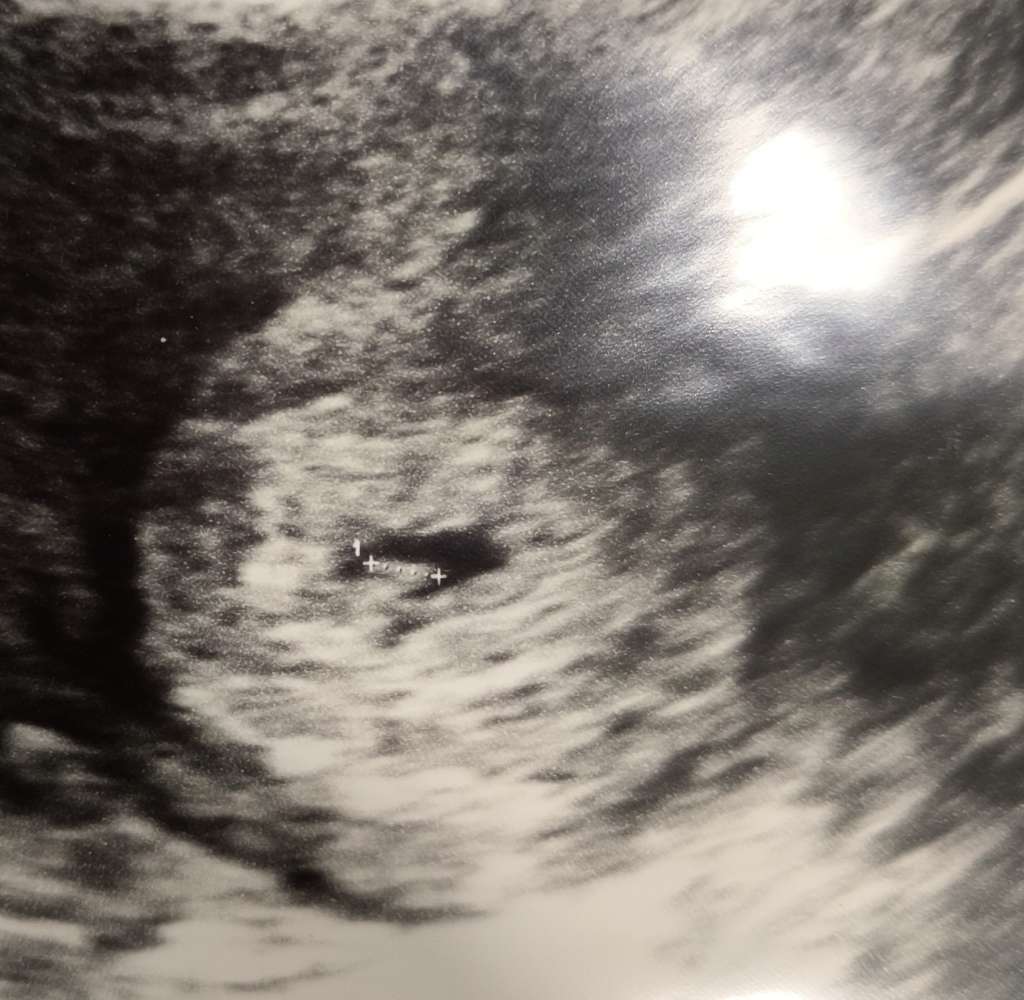

Jest już zarodek?Cześć ciotkiMamy 2 mm człowieka na swoim miejscu

Tak na razie bez serduszka bo to za wcześnie, ale jestJest już zarodek?![]()